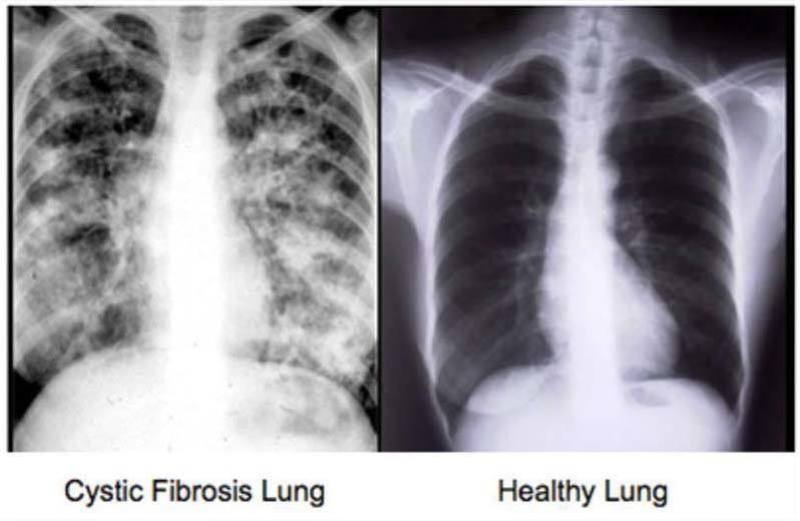

Effect on lung

Image

If a bad lung infection occurs, which can happen often in some individuals, intravenous antibiotics are required, which may have to be administered in hospital.

For many people with CF a double lung transplant becomes the only option. While this tends to improve quality of life, the operation comes with risks and after a transplant certain drugs are required to prevent the donor organs from being rejected.